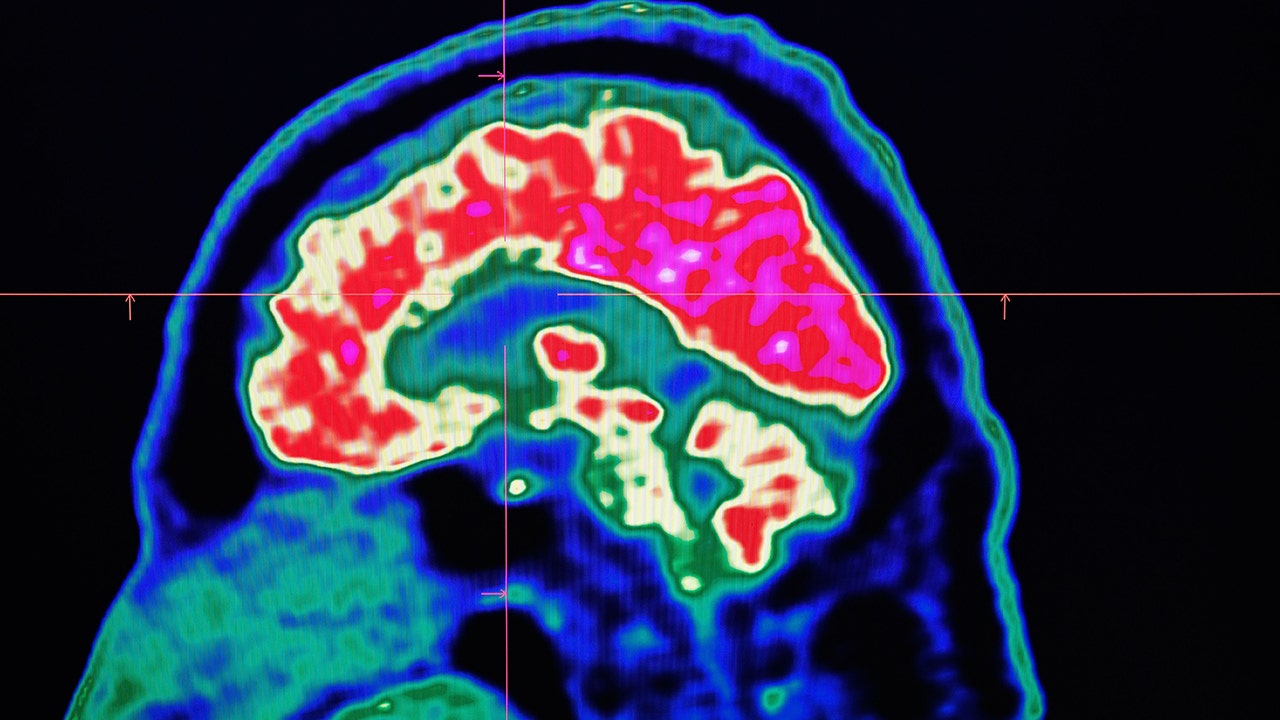

A picture of a human brain taken by a positron emission tomography scanner, also called PET scan, is seen on a screen on January 9, 2019. (Credit: FRED TANNEAU/AFP via Getty Images)